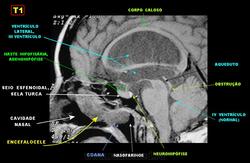

Цефалоцеле

Приложения:

1._cef.slayd98.jpg